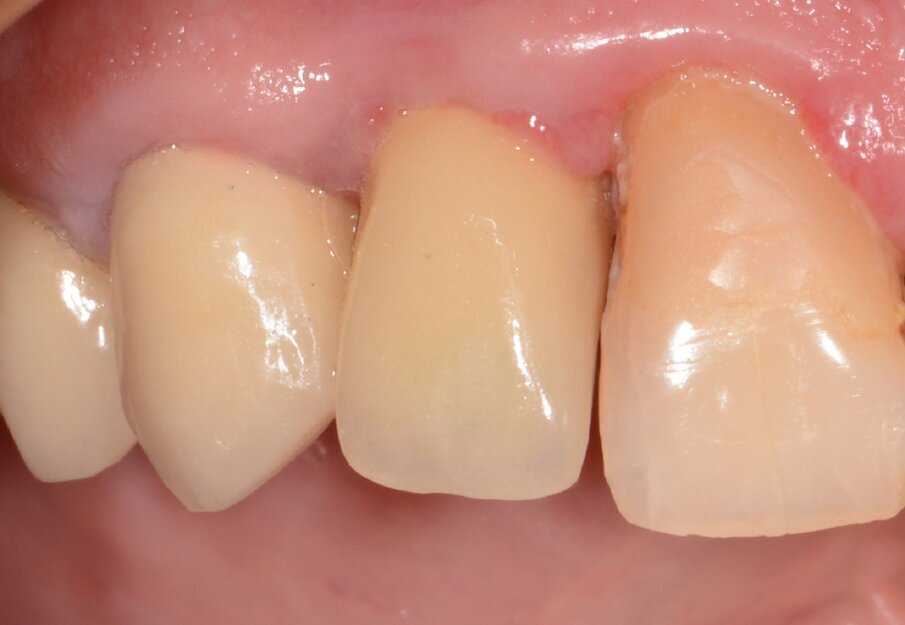

Fig. 20: Situation 1.5 years post-op. No sign of inflammation.

Fig. 7: Final results after three months. No sign of inflammation.